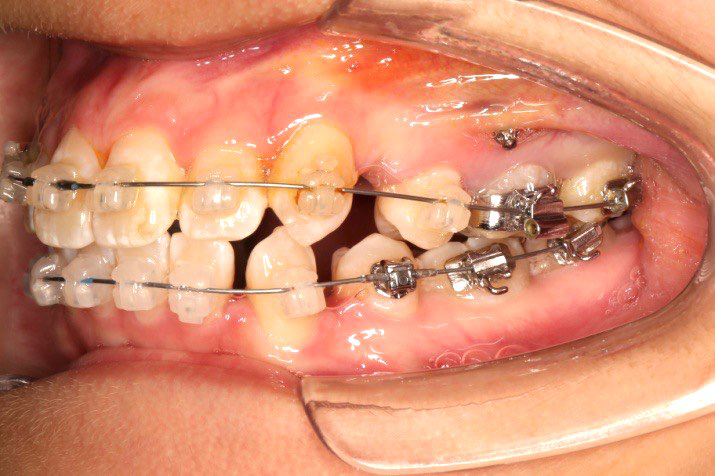

2017.10.07

2017.10.07  继续关间隙,下颌使用水平关间隙

下颌磨牙通过powerarm直立效果明显,下颌整平效果明显

2017.12.15  继续关间隙

2018.03.01上TPA加17、27颚侧牵引钩,压低17、27颚尖下颌43、32重粘,下颌0.016*25niti

2018.04.20  间隙基本关闭,上颌重新整平,精调